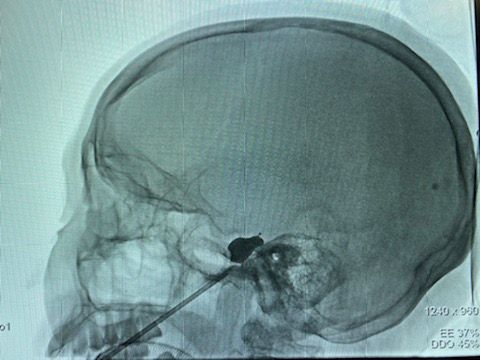

如果正常三叉神经痛患者,术中显示该球囊,术后效果疼痛缓解没问题,但该患者累及右侧头皮疼痛,所以,球囊导管需要再次调整。

经皮穿刺微球囊压迫三叉神经节治疗复发性三叉神经痛